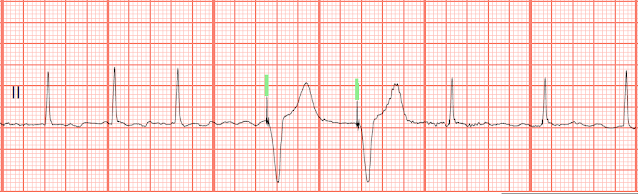

02. Identify the following rhythm.

a. Sinus rhythm with bigeminal PVCs

b. Sinus rhythm with unifocal PVCs

c. Sinus rhythm with multifocal PVCs

d. Sinus rhythm with a brief run of VT

02. a. Sinus rhythm with bigeminal PVCs